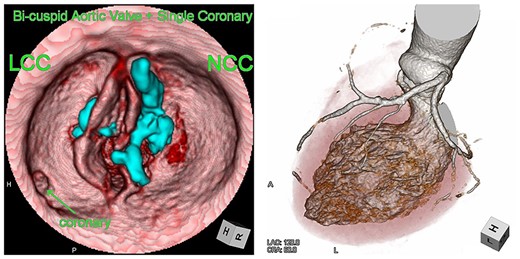

We report the case of an 82-year-old female with severe BAV stenosis type 0 and single coronary artery (Fig. 1). Given the risk profile and her preference, the decision was made for TAVR rather than surgical AVR. In the operating room (OR), we barely advanced the hard wire across the aortic valve due to the extensive calcification on the non-coronary cusp (NCC). Finally, a transcatheter heart valve (THV) was deployed under fibrillatory arrest, however the expansion of THV was suboptimal especially around the lower portion of THV close to the aortic annulus probably due to the hard extensive NCC calcification (Fig. 2). The balloon valvuloplasty was performed and she was taken back to the intensive care unit. Given the renal failure and patient’s age, further intervention was not recommended at this point.

Computed tomography images of the bicuspid aortic valve type 0 and single coronary artery. Heavy calcification on NCC is indicated in blue.